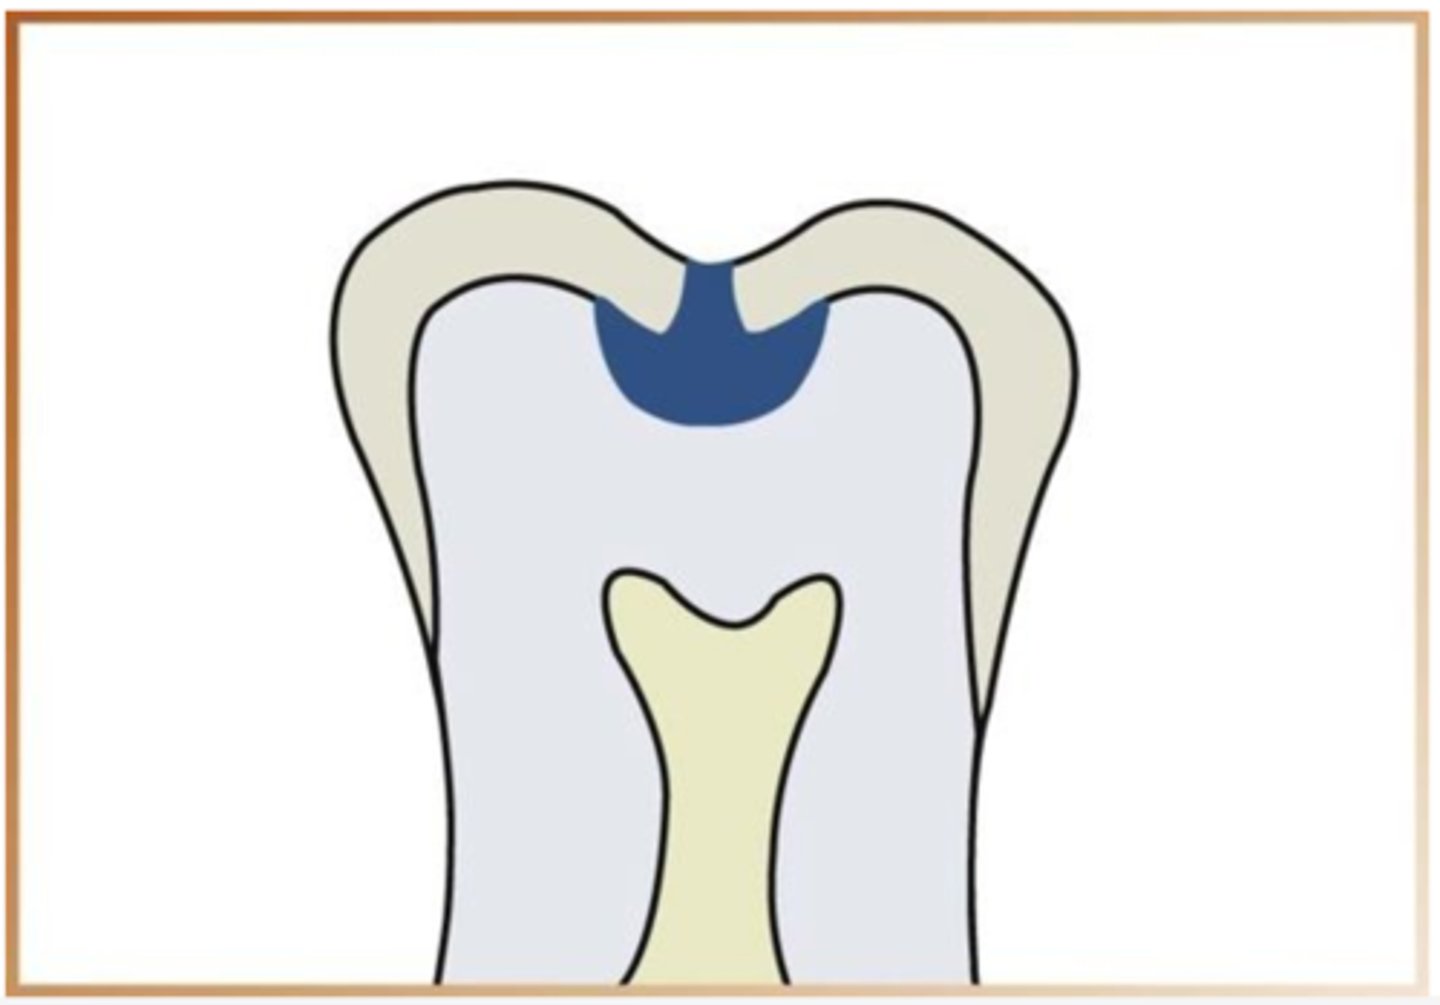

what is a class I interproximal caries

extends less than halfway through enamel

what is class II interproximal caries

extends more than half way through the enamel

what is a class III interproximal caies

extends to or through the DEJ and into dentin

what is class IV inerproximal caries

extends through enamel and dentin more than half distance towards the pulp